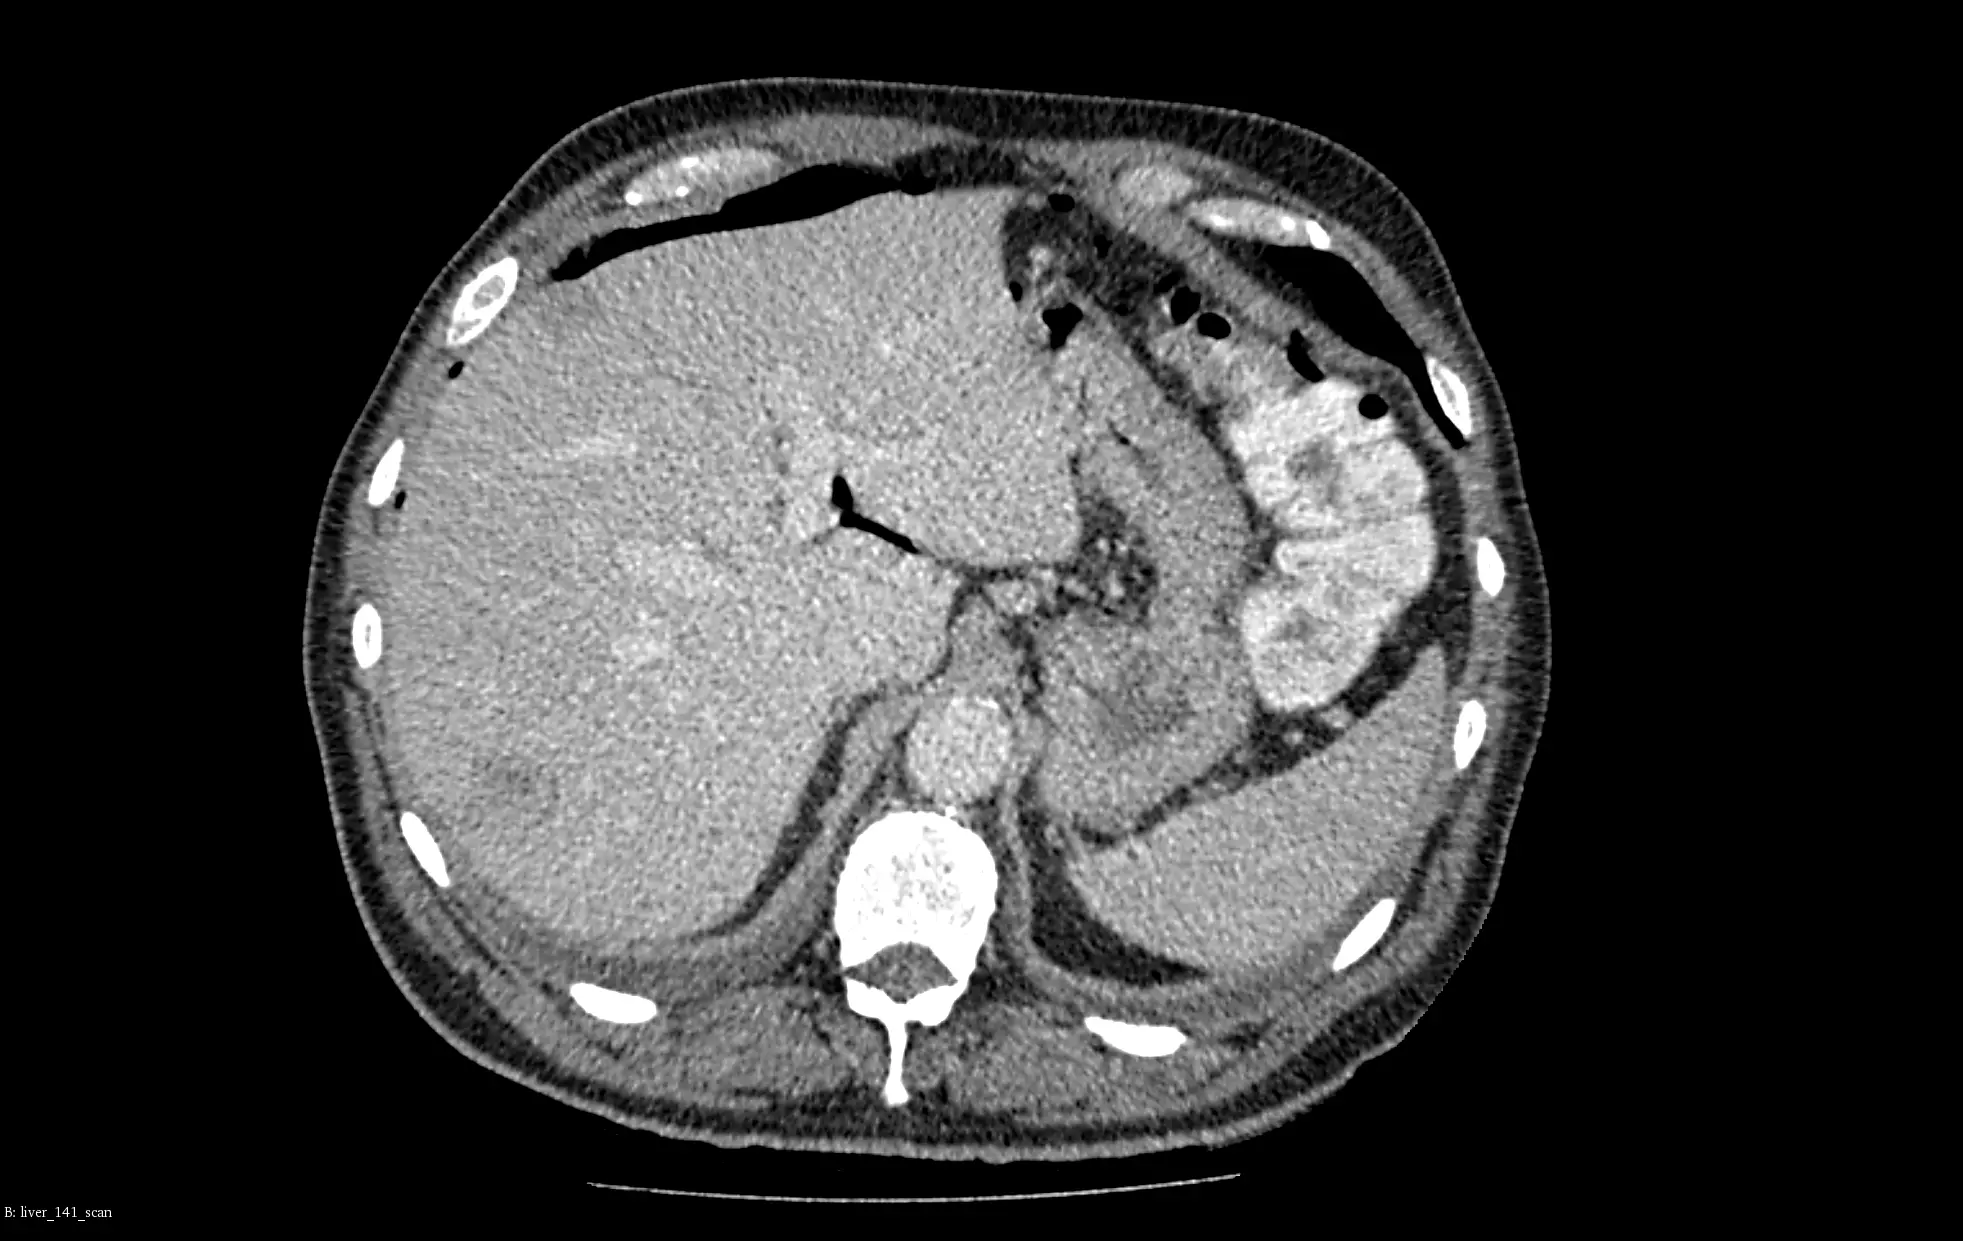

In the above example, we present our models for liver and liver tumor segmentation. The image shows primary tumors, secondary tumors and metastases. It is based on portal venous CT scans. For clarity, only the two biggest lesions are marked in the visualizations.